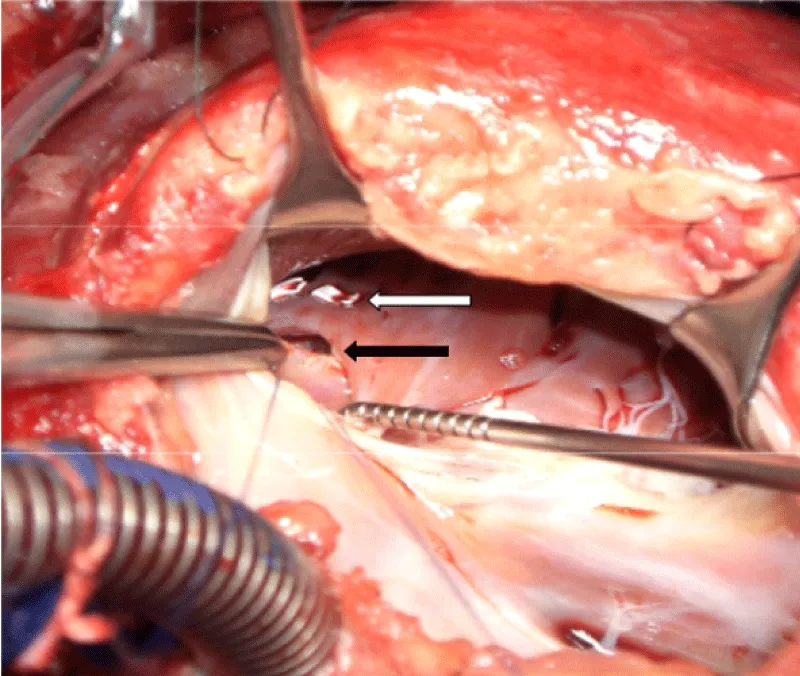

The electrocardiogram recorded a regular sinus rhythm. The X-ray showed a more marked bilateral effusion on the left, flaky opacities at the two hiles and cardiomegaly (Figure 1).

Figure 1: Chest X-ray showing alveolar edema, pleural effusion and enlarged cardiac silhouette.